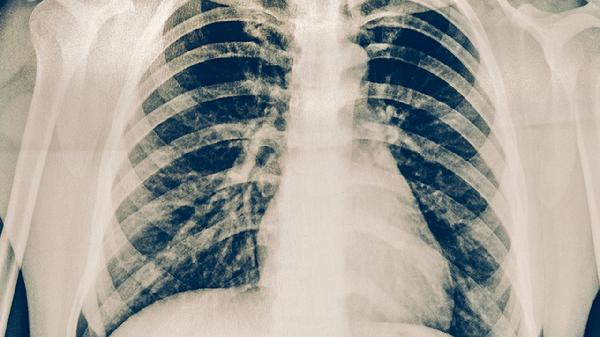

肺結(jié)核的預(yù)防方法主要有接種卡介苗、避免接觸傳染源、增強(qiáng)免疫力、保持環(huán)境衛(wèi)生、及時(shí)就醫(yī)治療等。

卡介苗是預(yù)防結(jié)核病的有效疫苗,通常在新生兒出生后24小時(shí)內(nèi)接種。卡介苗能夠顯著降低兒童重癥結(jié)核病的發(fā)生概率,但對(duì)成人肺結(jié)核的預(yù)防效果有限。接種后可能出現(xiàn)局部紅腫或潰瘍,屬于正常免疫反應(yīng)。

肺結(jié)核主要通過(guò)空氣飛沫傳播,應(yīng)避免與活動(dòng)性肺結(jié)核患者密切接觸。在人群密集場(chǎng)所佩戴口罩,保持1米以上社交距離。若家庭成員確診,需單獨(dú)居住并做好通風(fēng)消毒,接觸時(shí)佩戴N95口罩。

出現(xiàn)咳嗽咳痰超過(guò)2周、低熱盜汗等癥狀時(shí),應(yīng)立即到結(jié)核病定點(diǎn)醫(yī)療機(jī)構(gòu)檢查。確診后規(guī)范服用異煙肼片、利福平膠囊、吡嗪酰胺片等抗結(jié)核藥物6-8個(gè)月。治療期間需定期復(fù)查肝腎功能,不可擅自停藥以防產(chǎn)生耐藥性。

預(yù)防肺結(jié)核需采取綜合措施,高危人群如糖尿病患者、免疫抑制患者、密切接觸者等應(yīng)定期進(jìn)行結(jié)核菌素試驗(yàn)或γ-干擾素釋放試驗(yàn)篩查。日常生活中注意咳嗽禮儀,養(yǎng)成不隨地吐痰的良好衛(wèi)生習(xí)慣。出現(xiàn)可疑癥狀時(shí)避免隱瞞病情,早診斷早治療既可提高治愈率,也能減少傳播風(fēng)險(xiǎn)。結(jié)核病患者飲食應(yīng)保證充足熱量和蛋白質(zhì),適當(dāng)補(bǔ)充維生素A、D、E等有助于黏膜修復(fù)的營(yíng)養(yǎng)素。